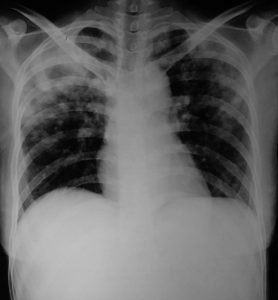

उत्तर प्रदेश औरैया जिला क्षय रोग अधिकारी डॉ. संत कुमार ने बताया कि फेफड़े की टीबी को पल्मोनरी और शरीर के अन्य हिस्से की टीबी को एक्स्ट्रा पल्मोनरी टीबी कहा जाता है। टीबी के मरीजों में करीब 70 फीसदी में पल्मोनरी और 30 फीसदी में एक्स्ट्रा पल्मोनरी टीबी होती है। एक्स्ट्रा पल्मोनरी टीबी से ग्रसित मरीजों से दूसरों को खतरा कम होता है, जबकि पल्मोनरी टीबी दूसरों को ज्यादा संक्रमित कर सकता है। एक्स्ट्रा पल्मोनरी टीबी जिसे होता है, उसे सूजन, दर्द, हल्का बुखार, रात में पसीना, भूख नहीं लगती है। डॉ.कुमार ने बताया कि एक्स्ट्रा पल्मोनरी टीबी पल्मोनरी टीबी के साथ भी हो सकती है। इस प्रकार की टीबी अधिकतर कमजोर प्रतिरोधक क्षमता वाले लोगों और छोटे बच्चों में अधिक पायी जाती है। एचआईवी से पीड़ित लोगों में, एक्स्ट्रा पल्मोनरी टीबी की संभावना अधिक होती है। एक्स्ट्रा पल्मोनरी टीबी को अंगों के हिसाब से नाम दिया गया है। मुख्यत: हड्डी, रीढ़ की हड्डी, आंत, गले की कंठमाला और फेफड़ों में पानी का उतर आना एक्स्ट्रा पल्मोनरी टीबी की श्रेणी में आते हैं।

जिला कार्यक्रम समन्वयक श्याम कुमार ने बताया कि वर्ष 2022 में जनवरी माह से नवम्बर माह तक 1657 लोगों में एक्स्ट्रा पल्मोनरी टीबी की पुष्टि हुई है ।

जिला पीपीएम समन्वयक रविभान सिंह ने बताया कि दो सप्ताह या अधिक समय तक खांसी आना, खांसी के साथ बलगम आना, बलगम में कभी-कभी खून आना, सीने में दर्द होना, शाम को हल्का बुखार आना, वजन कम होना और भूख न लगना सामान्य लक्षण हैं। ऐसे लक्षण मिलने पर तत्काल जांच कराएं।